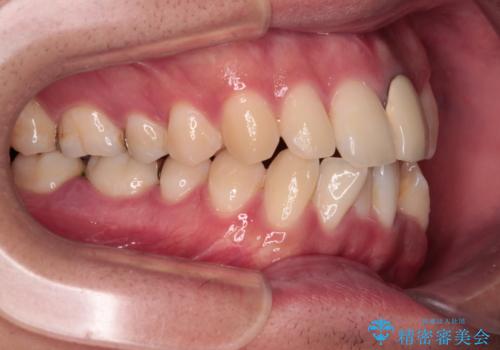

上下ともに歯列幅が狭く、その影響でデコボコになっていたため、ワイヤー装置を用いて歯列を側方に拡大しながら、デコボコを解消していくこととしました。

矯正治療後には気になっていた前歯をセラミッククラウンにし、自然な口元に仕上げることができました。